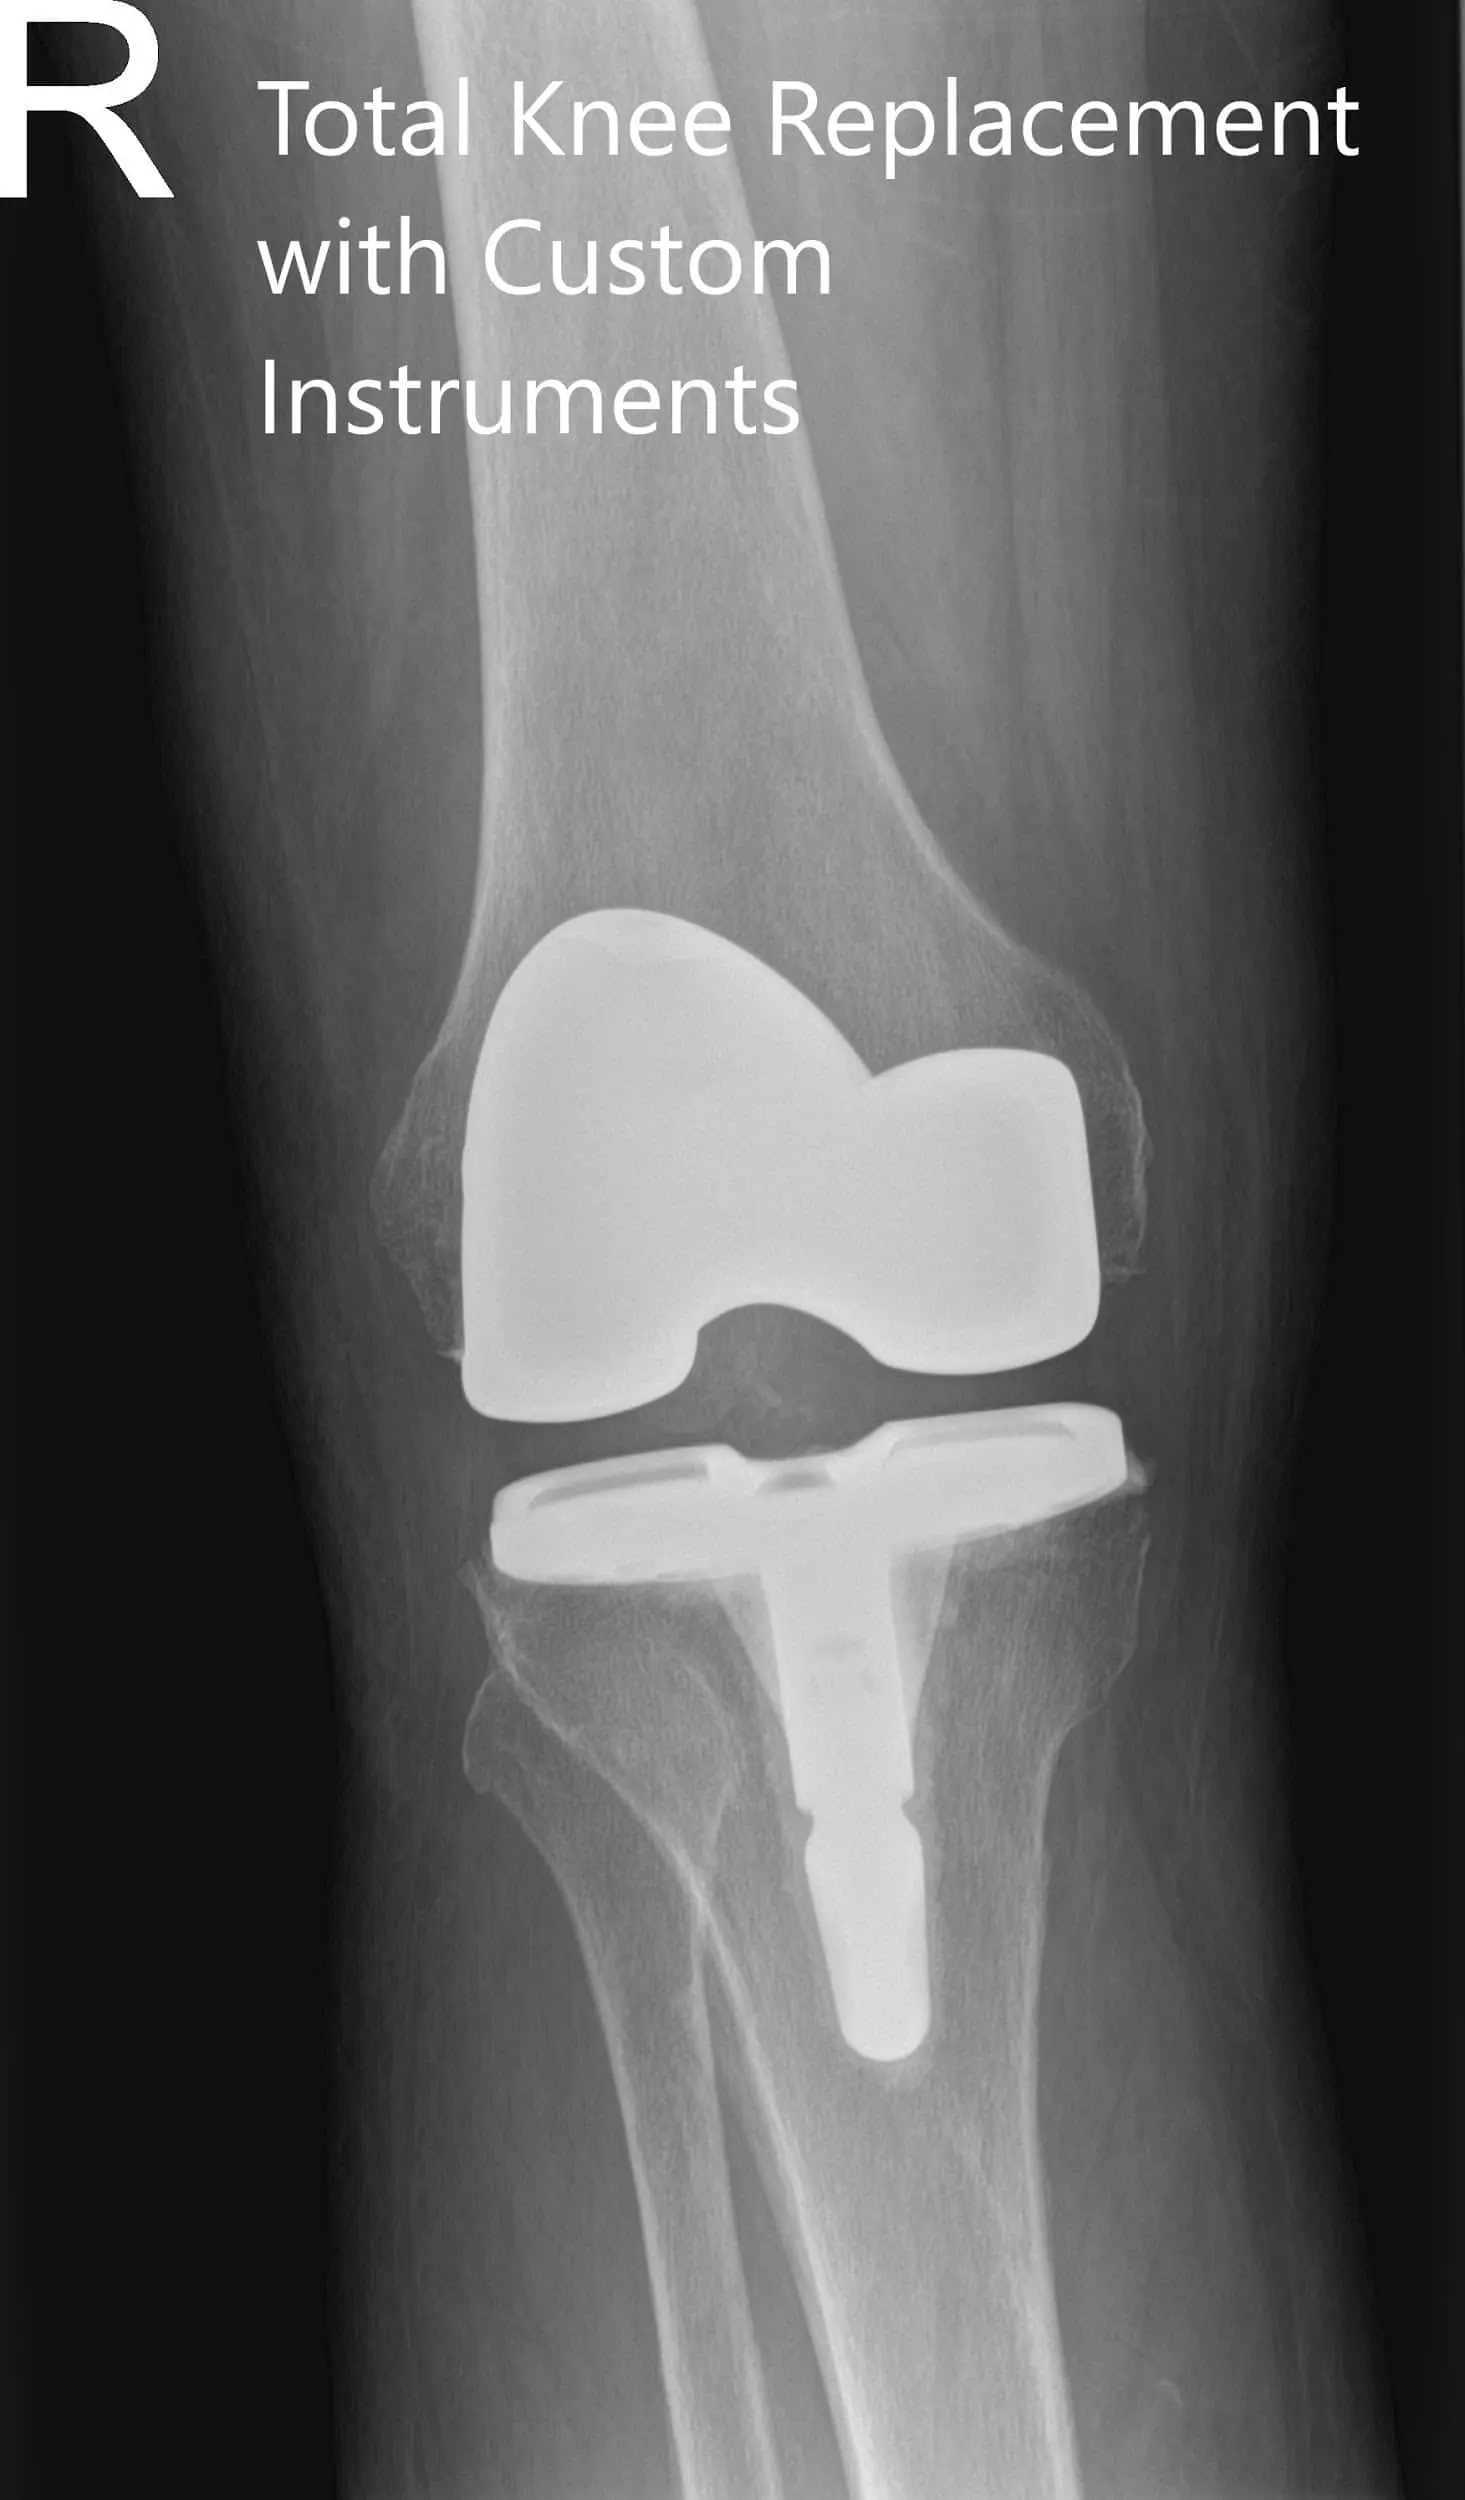

ostoperative X-ray of the right knee in anteroposterior and lateral views

Postoperative X-ray of the right knee in anteroposterior and lateral views.